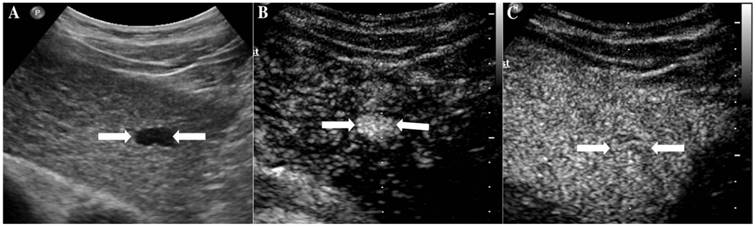

At last, of the 37 observations classified as LR-5, 33 (89.19%) were pathologically confirmed as malignant including 1 ICC (2.7%) and 32 HCC (86.49%). The typical ultrasound images are shown in Figure 1. However, 4 lesions (10.81 %) were histologically proved to be benign, 3 regenerative nodule (8.11%) (Figure 2) and 1 focal nodular hyperplasia (2.7%). With respect to the 8 LR-4 observations, 4 cases (50%) turned out to be HCCs (Figure 3). Angioma, focal nodular hyperplasia (Figure 4) and regenerative nodule accounts for 12.5% (1/8), 12.5% (1/8) and 25% (2/8) respectively. Nine observations categorized as LR-M consist of 7 (77.78%) HCC (Figure 5), 1 (11.11%) ICC and 1 (11.11%) RLH, based on pathological findings. The correct diagnoses of HCC, ICC and benign lesions were used to measure diagnostic accuracy for LI-RADS-CEUS. An example of successful categorization of HCC as LR-3 was shown in Figure 6. For the diagnosis of HCC, the overall diagnostic accuracy of LR-5 was 86.49 % (32/37) and that of LR-4 was 50% (4/8). However, the diagnostic accuracy of LR-M was only 11.11% in the retrospective study (Table 3).

Figure 1

The assigned LI-RADS category of this patient was LR-5. Hepatocellular carcinoma (HCC) was confirmed by histopathology. A. Conventional B-mode image showed a hypoechoic nodule (arrows) of about 1.8cm on the right hepatic lobe of a 52-year-old male patient. B. CEUS showed hyperenhancement (arrows) in arterial phase. C. CEUS showed hypoenhancement (arrows) in the late phase.